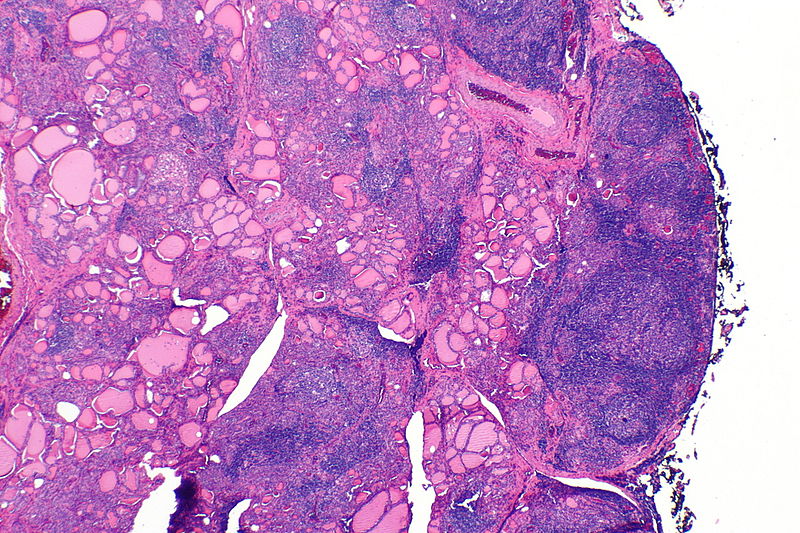

Histologically, Hashimoto thyroiditis shows chronic inflammation with germinal centers and Hürthle cells is associated with eosinophilic metaplasia of cells lining follicles.

Follicular thyroid adenoma is characterized by a benign proliferation of follicles encased in an inactive fibrous capsule.

Follicular thyroid adenoma does not invade the capsule.

Follicular thyroid carcinoma (FTC) is the malignant proliferation of thyroid follicles with invasion through the capsule.

Follicular thyroid carcinoma invades the capsule.

The distinction between a follicular adenoma and a follicular carcinoma cannot be made by fine needle aspiration (FNA) because FNA only looks at the cells and not the entire capsule under a microscope.